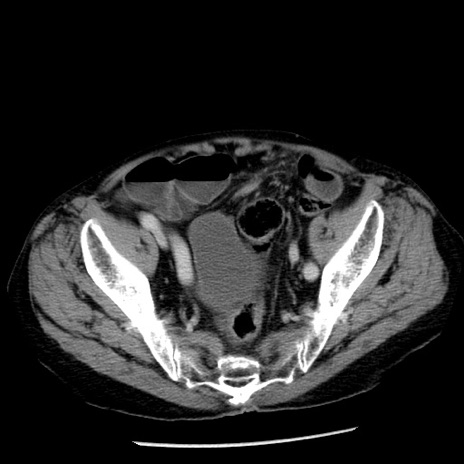

症例26(横断像)

【症例】80歳代男性

【主訴】嘔吐

【現病歴】昨晩2回嘔吐あり、今朝になっても嘔吐あり。来院。

【既往歴】胃潰瘍

【身体所見】意識清明、BT 37.6℃、BP 166/95mmHg、HR 100bpm、SpO2 97%、腹部:平坦・軟、腸蠕動音聴取良好、圧痛なし。

【データ】WBC 21900、CRP 1.46